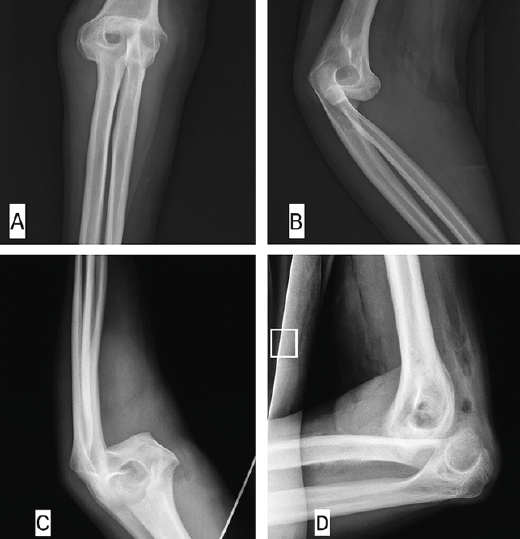

A 42-year-old right-handed male construction worker fell from a scaffold approximately 10 feet high. He landed with both arms outstretched and elbows extended. Upon presentation, the patient had gross deformity, pain, and swelling at both wrists and elbows. Upon inspection, deformities were seen on both wrists and elbows bilaterally. On examination, tenderness was found with a limited range of motion. Neurovascularity was intact in both upper limbs. X-rays revealed bilateral posterior elbow dislocation without associated fracture (Fig. 1a, b, c, d) and bilateral comminuted intra-articular distal radius fractures (AO 23-C2). (Fig. 2a, b, c, d). In the emergency setting, both elbow dislocations were promptly managed with closed reduction under sedation, and concentric reduction was confirmed on post-reduction radiographs (Fig. 3a, b, c, d). Both wrists were also reduced, and stabilization was done with slab application (Fig. 4a, b, c, d). Following initial stabilization and resolution of soft tissue swelling, the patient underwent staged open reduction and internal fixation of the bilateral distal radius fractures using a volar approach (modified Henry technique). Fixation was achieved using volar locking compression plates for both wrists (Fig. 5a, b, c, d).

Figure 1: X-rays showing posterior dislocation of the right elbow without any fracture in anteroposterior (a) and lateral (b) view and left elbow showing posterior dislocation of elbow without any fracture in anteroposterior (c) and lateral (d) view.